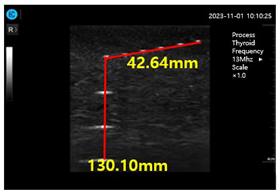

Figure 15a shows ultrasonic gel testing at various time intervals using the ATS-539 phantom. Figure 15b shows the sharpness of the image of the manufactured gelatin soft gel after storing it in alcohol and performing a sharpness test at 1 h intervals for 72 h. The results are presented in Figure 15b. In this paper, the experiment using a soft solid gel did not require IRB agreement. This research on the proposed gelatin soft solid gel showed its functionality to be better than that of ultrasonic gel, including on grayscale, echo, and color. This means that it can overcome the tissue density dead zone to increase high resolution performance. To help imaging accuracy, it is proven that gelatin soft gel, especially the soft solid gel, can replace ultrasonic gel to simplify disinfection and ensure permanent use. Image corrosion testing of gelatin soft solid gel for 30 min is shown in Figure 16a. Ultrasonic gels were tested at different times using an ATS-539 phantom, where the gel was soaked in ethanol for 72 h, as shown in Figure 16b. Afterwards, the gel’s condition was tested again. Finally, Figure 16c measures the imaging resolution of the gelatin soft tissue gel.